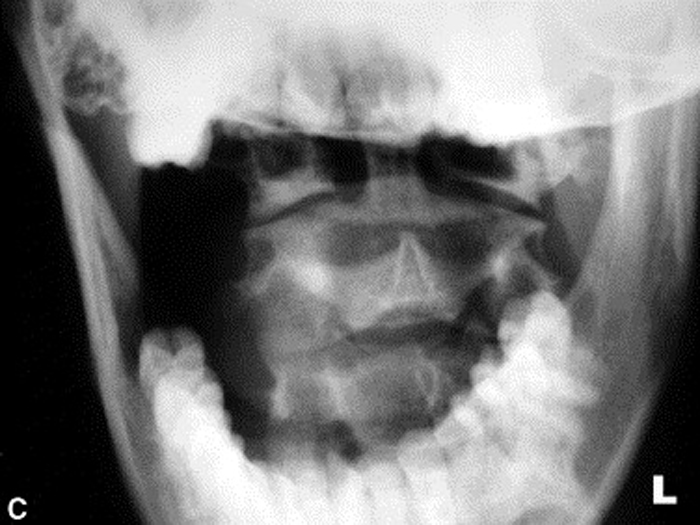

Radiographs were ordered (Figure 1, A through C) due to the longevity of the complaint and revealed a persistent narrowing of the left para-odontoid space. The radiology report stated that the asymmetry might be due to a right rotational malposition of atlas, possibly a compensatory response to a left rotational fixation of axis.

Figure 2.

B: Neutral and angulated anteroposterior open month

radiographs reveal a narrowed left para-odontoid space.